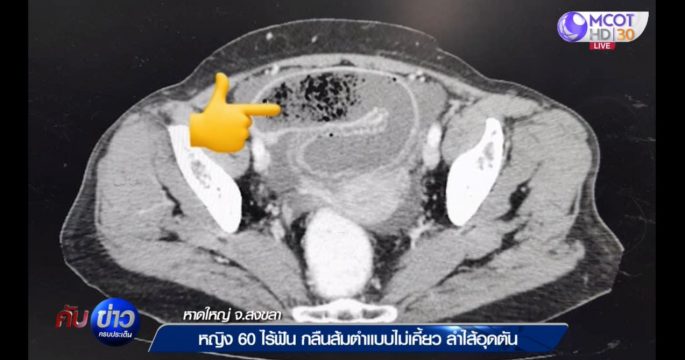

จากกรณียายกลืนกินส้มตำโดยไม่เคี้ยว วันนี้ทีมข่าวบุกร้านส้มตำ พิสูจน์เส้นมะละกอที่นำมาทำส้มตำ ว่าเส้นใหญ่ขนาดไหน พอจะกลืนโดยไม่เคี้ยวได้หรือไม่ ด้านแม่ค้าตกใจว่าทำได้อย่างไร แค่เคี้ยว 2 คำ 3 คำยังกลืนไม่ได้เลย

หญิงอายุ 60 ปี ไม่มีฟัน ซื้อส้มตำมากินแบบกลืนโดยไม่เคี้ยว ทำป่วยเป็นลำไส้อุดตัน ต้องผ่าตัดนอนรักษาตัวโรงพยาบาลนานครึ่งเดือน